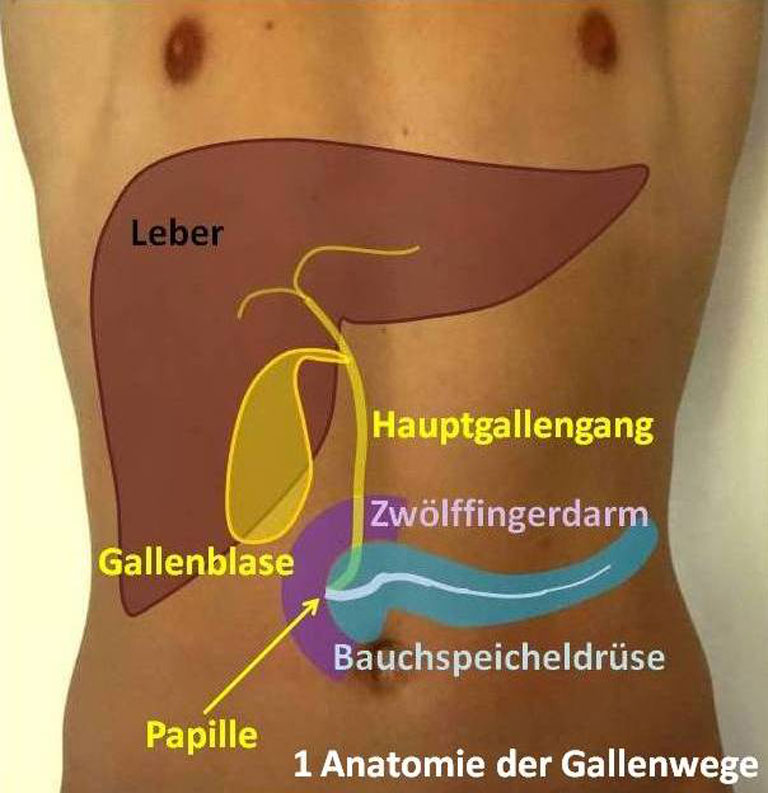

Bij een galwegontsteking (cholangitis) zijn de galwegen in of buiten de lever ontstoken. In de lever zitten veel kleine galkanaaltjes. Deze komen samen in de grotere galwegen. Via de grotere galwegen wordt de galvloeistof afgevoerd naar de galblaas en vervolgens naar de dunne darm. De galblaas.. Auszug. Die extra hepatischen Gallen wege in Form des Gallengangs und der Gallenblase garantieren den großen täglichen Bedarf an fettemulgierender Galle. Jede Unwegsamkeit darin provoziert ein Stenosemuster mit entsprechendem Gallenrückstau, der akut zum tödlichen Leberversagen und chronisch zu einem fibrodestruktiven Reaktionsmuster und.

De galblaas. Anatomie van de galblaas en galwegen. Anatomie van de twaalfvingerige darm en de

Lever (Hepar)Galwegen en Galblaas